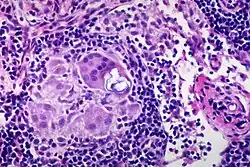

Schaumann body

In pathology, Schaumann bodies are calcium and protein inclusions inside of Langhans giant cells as part of a granuloma.

Many conditions can cause Schaumann bodies, including:

- Sarcoidosis,

- Hypersensitivity pneumonitis, and

- Berylliosis.

- uncommonly, Crohn's disease and tuberculosis.[1]